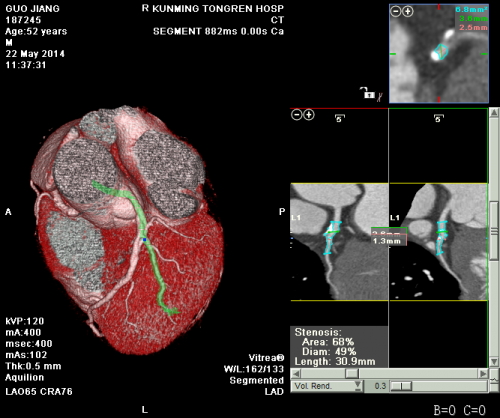

我院影像科冠状动脉CT造影片如下图: